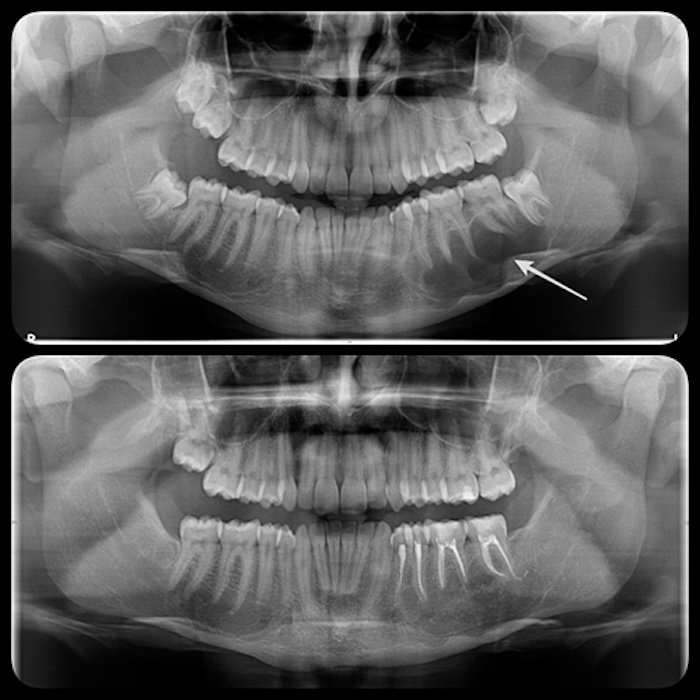

Un diente incluido en el hueso (quiste folicular), una infección crónica o un tejido anómalo (quistes o tumores odontogénicos) pueden ser la causa de un quiste en el espesor de los huesos maxilares. Los más frecuentes, llamados quistes radiculares, se producen por infecciones crónicas de origen dental.

Los quistes al crecer, van destruyendo el hueso adyacente y formando grandes cavidades en el interior del maxilar o la mandíbula. También se pueden infectar, por todo ello deben ser extirpados quirúrgicamente y eliminar todos sus restos para evitar que se reproduzca. Se trata de una intervención sencilla y si el quiste no es de gran tamaño se puede realizar bajo anestesia local.